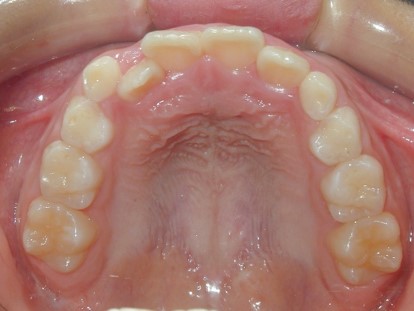

永久歯に交換するためのスペース不足による前歯のガタガタで、取り外しができる拡大床にて上下顎の幅を拡大した後、上顎の前歯をマルチブラケット装置で並べました。治療の期間は1年9か月でした。

初診時

終了時